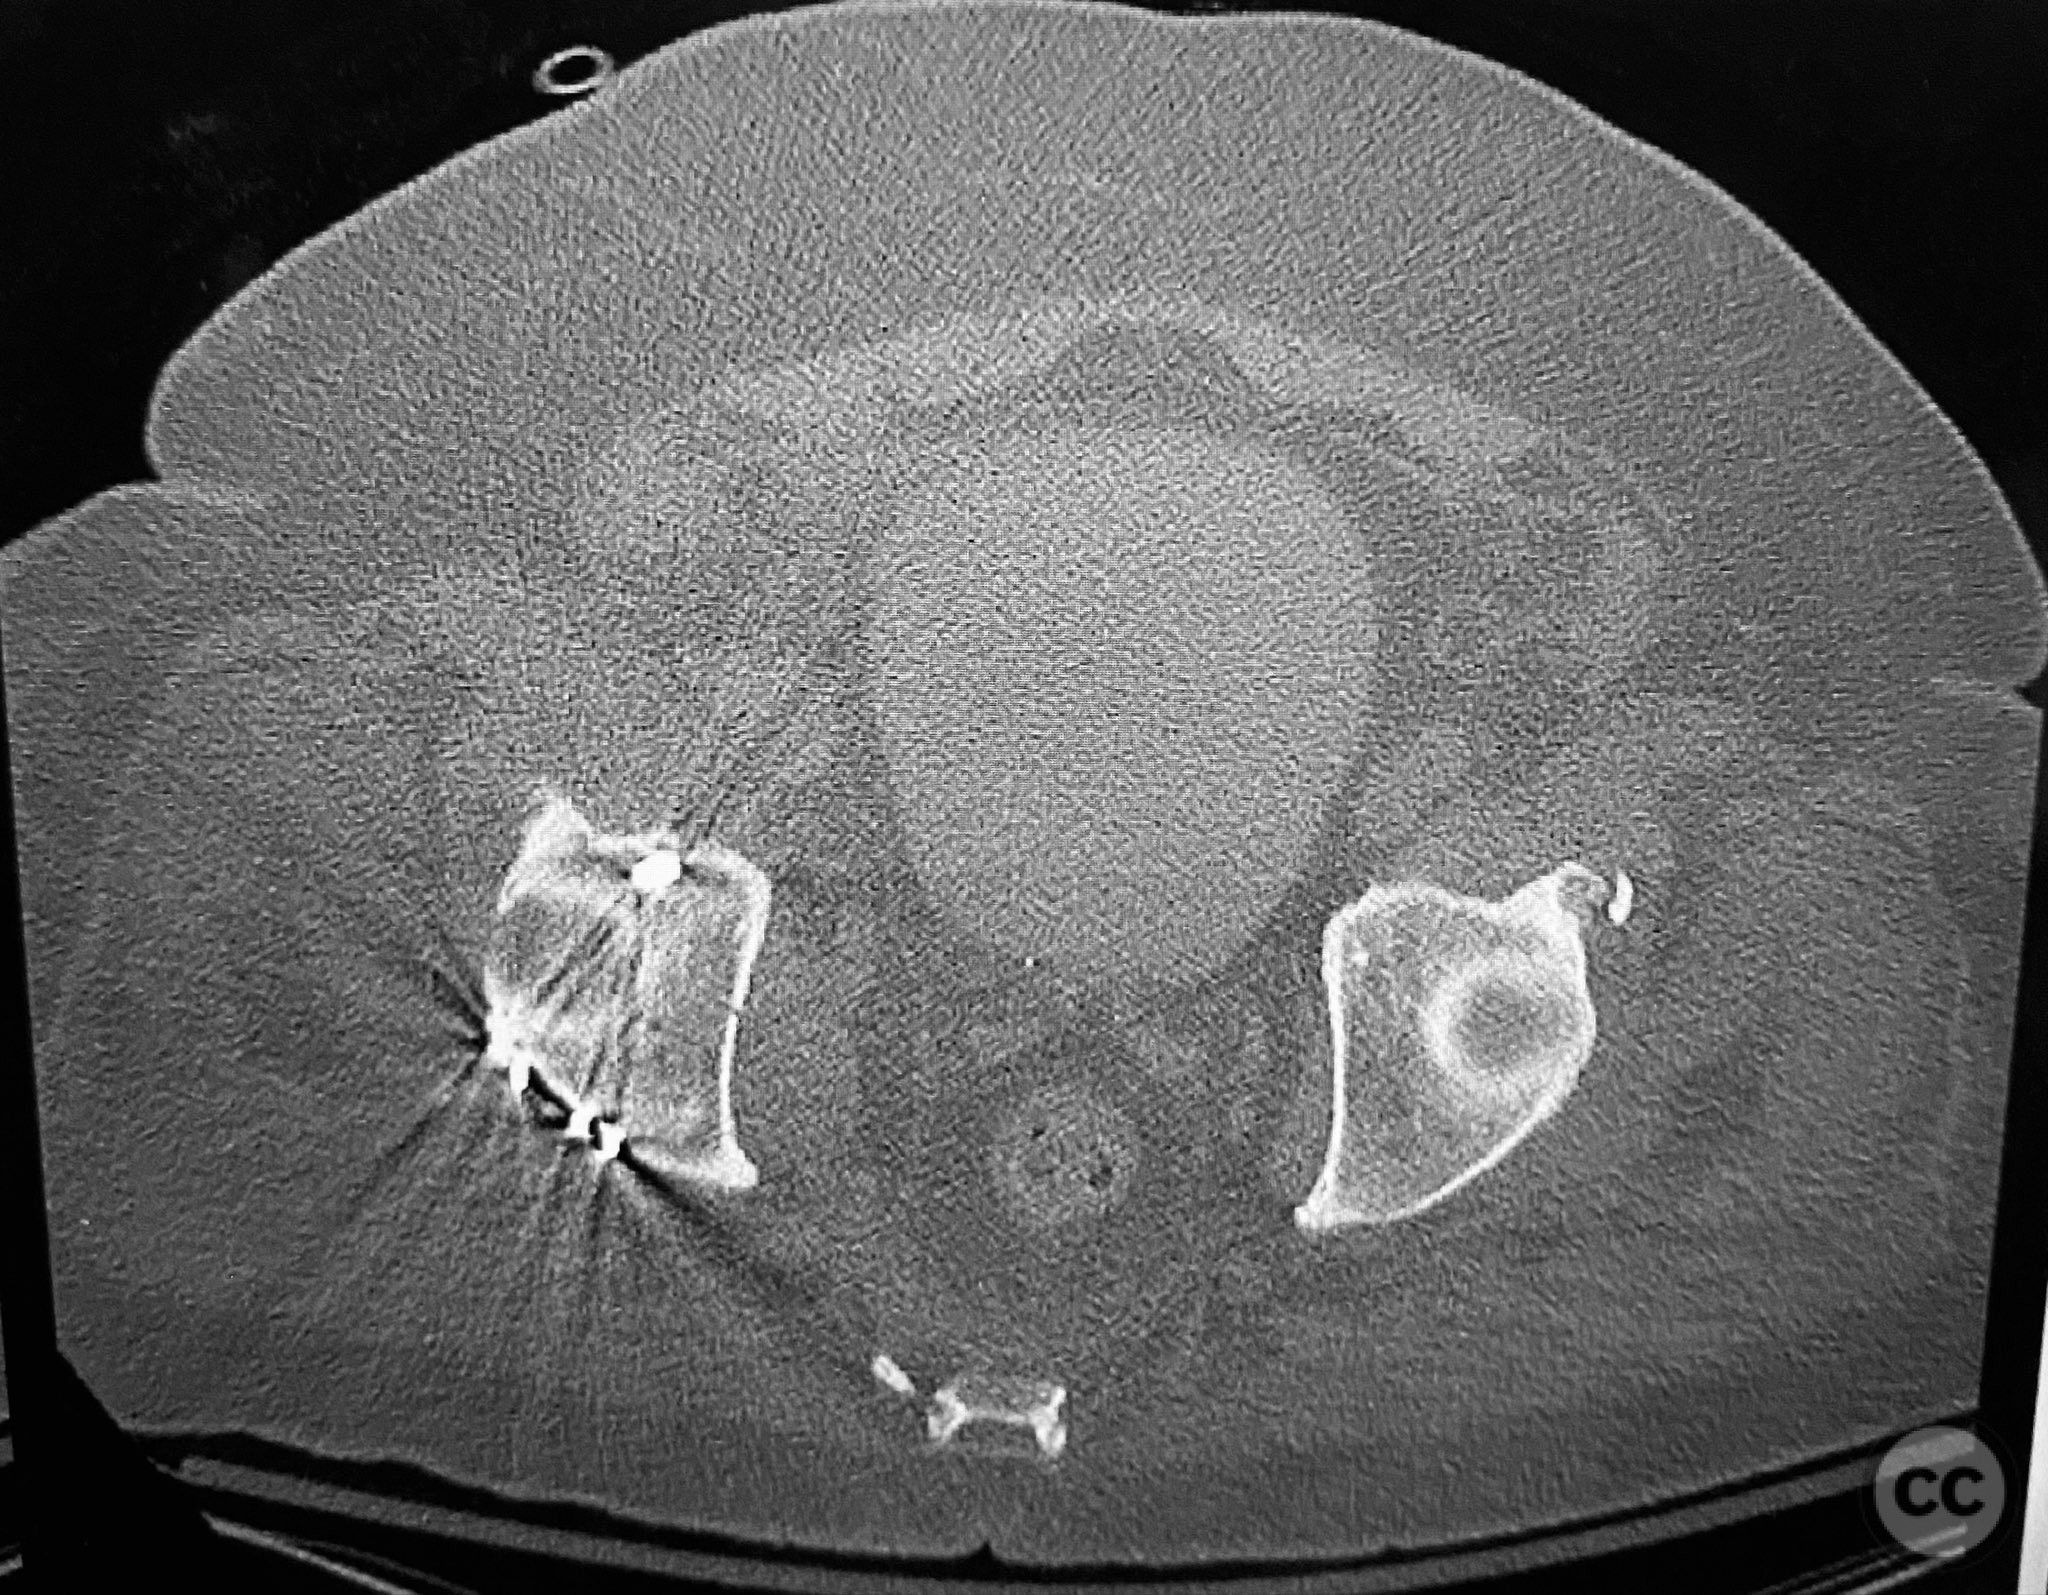

Clinical Details

Clinical and radiological findings:  A 79-year-old male sustained a high-energy injury in a motor vehicle collision, resulting in a complex acetabular fracture-dislocation. Radiographs and computed tomography demonstrated a posterior wall and transverse acetabular fracture (AO/OTA 62-B1.3), with the posterior wall fragments displaying an atypical caudal hinge configuration. The medial wall fragment was non-articular. Axial imaging revealed an impacted osteochondral fragment obstructing reduction, as well as disruption of the capsular structures adjacent to the intact articular segment. The obturator internus tendon appeared taut but intact, with no evidence of sciatic nerve impingement or superior gluteal neurovascular compromise.

Orthopaedic implants used:   3.5mm pelvic reconstruction plate (posterior wall), 3.5mm pelvic reconstruction plate (medial wall), percutaneous cannulated lag screw, cancellous bone graft